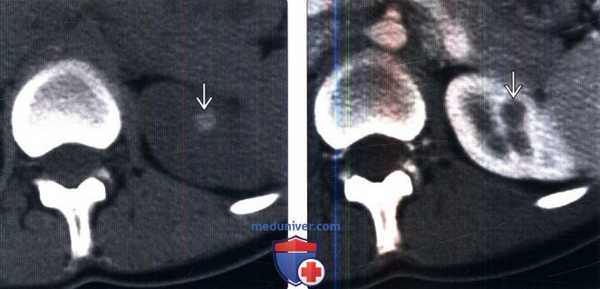

(Слева) КТ без контрастирования, аксиальная проекция: гиперденсная (100 HU) киста ВЗ левой почки (класс 2 по Босняку).

(Справа) КТ с контрастированием, аксиальная проекция: у того же пациента выявлено контрастирование кисты левой почки (106 HU). Гиперденсные кисты почки, имеющие плотность более 70 HU на бесконтрастной КТ, считают доброкачественными. Образования мягкотканной плотности (20-70 HU) на бесконтрастной КТ следует оценивать с помощью УЗИ или с использованием специализированного почечного КТ-протокола для дифференцирования истинных солидных образований от гиперденсных кист.